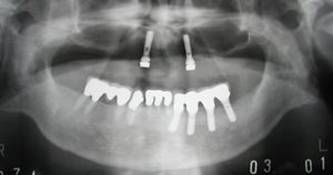

術後。上部構造はハイブリッドレジンです。しっかり嚙めるようになり喜んでいただきました。

上顎

下顎

治療後。歯周病で失われた骨が回復しています。使用インプラントはスプラインツイストです。

上部構造装着後6年。ハイブリッドレジンを使用したため、少し艶がなくなってきました。上部構造の材料には金属、ハイブリッドレジン、セラミックなどがあります。セラミックはきれいですが欠けやすいため、最近はフルジルコニアを使っています。

インプラント装着後6年。順調に経過しています。12か月毎のメインテナンスをしています。